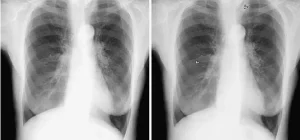

- Göğüs Röntgeni: Apikal akciğer nodüllerinin tespiti için ilk adım genellikle göğüs röntgenidir. Ancak, küçük nodüller röntgende net bir şekilde görülemeyebilir.

- Bilgisayarlı Tomografi (BT): Daha ayrıntılı bir görüntüleme yöntemi olan BT, apikal akciğer nodüllerinin yerini, boyutunu ve özelliklerini daha doğru bir şekilde belirleyebilir.